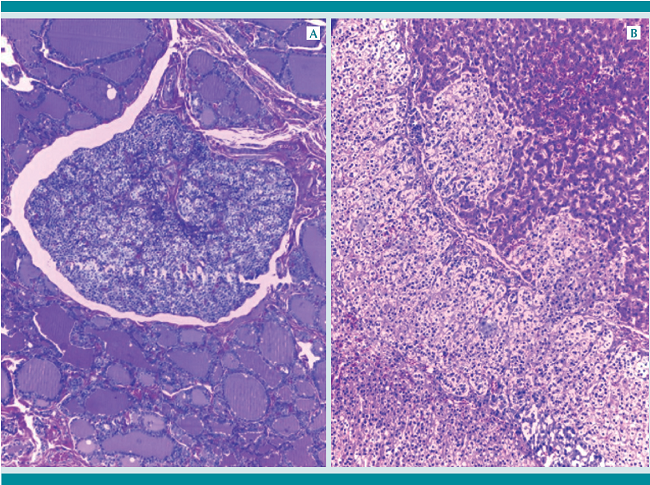

Más importante es la reconocida inmadurez pulmonar característica del niño con Down, con una menor población de alvéolos y un retraso en el desarrollo de la vascularidad pulmonar.7 (Figura 4B) Esto propicia el desarrollo de una hipertensión pulmonar grave, que fue lo que encontramos en esta niña; en todo el árbol arterial pulmonar se aprecia hipertrofia marcada de la capa muscular con disociación de las fibras elásticas; la microvascultura pulmonar mostraba arteriolización de los capilares intra-acinares con duplicación de la lámina elástica. (Figura 6)

La mayor susceptibilidad a la hipertensión arterial pulmonar es reconocida en el niño con síndrome de Down, sobre todo en residentes a altitudes relativamente altas como el altiplano mexicano, y que se presentan sin asociación necesaria con malformación cardiaca.8 La inmadurez alveolar, con pocos alvéolos y distendidos, en un paciente con reflujo gastroesofágico propicia problemas de aspiración; en la paciente encontramos material aspirado en bronquiolos y alvéolos. Probablemente, el bronquio traqueal derecho haya contribuido a problemas de aspiración aunque en la autopsia estos se encontraron en ambos pulmones. El avanzado estado de desnutrición y la propia respuesta inflamatoria débil del paciente con síndrome de Down puede explicar la ausencia de una reacción inflamatoria al material aspirado.